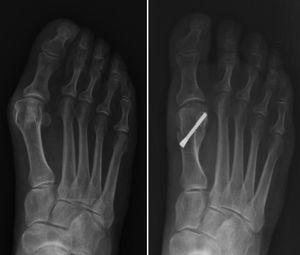

Técnica quirúrgica osteotomía en chevron percutáneaSe realiza bajo anestesia regional, mediante bloqueo selectivo en tobillo con guía ecográfica.

Se introduce una aguja de Kirschner de 2 mm subcutánea medial desde el extremo distal del hallux de manera retrógrada hasta la localización donde se realizará la osteotomía, en el cuello del primer metatarsiano.

A través de una incisión medial de 3 mm se realiza la osteotomía con una fresa tipo Shannon de 2 × 15 mm de largo, a nivel de la transición del cuello y la cabeza del primer metatarsiano. Se inicia el corte mediante un canal inicial paralelo a la superficie articular distal sobre el cuello del metatarsiano, que servirá de eje de la «v» y luego se completan las ramas a dorsal y plantar.

Se realiza el desplazamiento lateral de la cabeza, introduciendo la aguja de Kirschner endomedular desde la zona de la osteotomía con ayuda de una sonda acanalada.

Se fija la osteotomía de manera percutánea con dos tornillos a compresión de proximal a distal hacia la cabeza del metatarsiano. Cabe destacar que el primer tornillo colocado es el proximal, y este debe atravesar tres corticales a través de la osteotomía para una mejor fijación del tornillo (fig. 1).

Los ángulos radiológicos se compararon en el preoperatorio (Pre) y al final del seguimiento (Pop) de cada grupo (tabla 2). En el grupo de osteotomía en chevron percutánea mostraron cambios estadísticamente significativos en las tres variables consideradas, siendo las medias: AMTF pre: 25,42 (SD 6,45), pop: 9,7 (SD 6,5), p < 0,0001; AIM pre: 13,83 (SD 2,90), pop: 8,31 (SD 2,31), p < 0,0001; DMAA pre: 11,42 (SD 7,75), pop: 3,36 (SD 4,19).

En el grupo de osteotomía de Bosch también presentaron correlaciones estadísticamente significativas: AMTF pre: 25,31 (SD 7,63), pop: 7,41 (SD 5,31), p < 0,0001; AIM pre: 13,81 (SD 3,12), pop: 7,76 (SD 2,81), p < 0,0001; DMAA pre: 11,22 (SD 6,16), pop: 3,40 (SD 4,13), p < 0,0001.